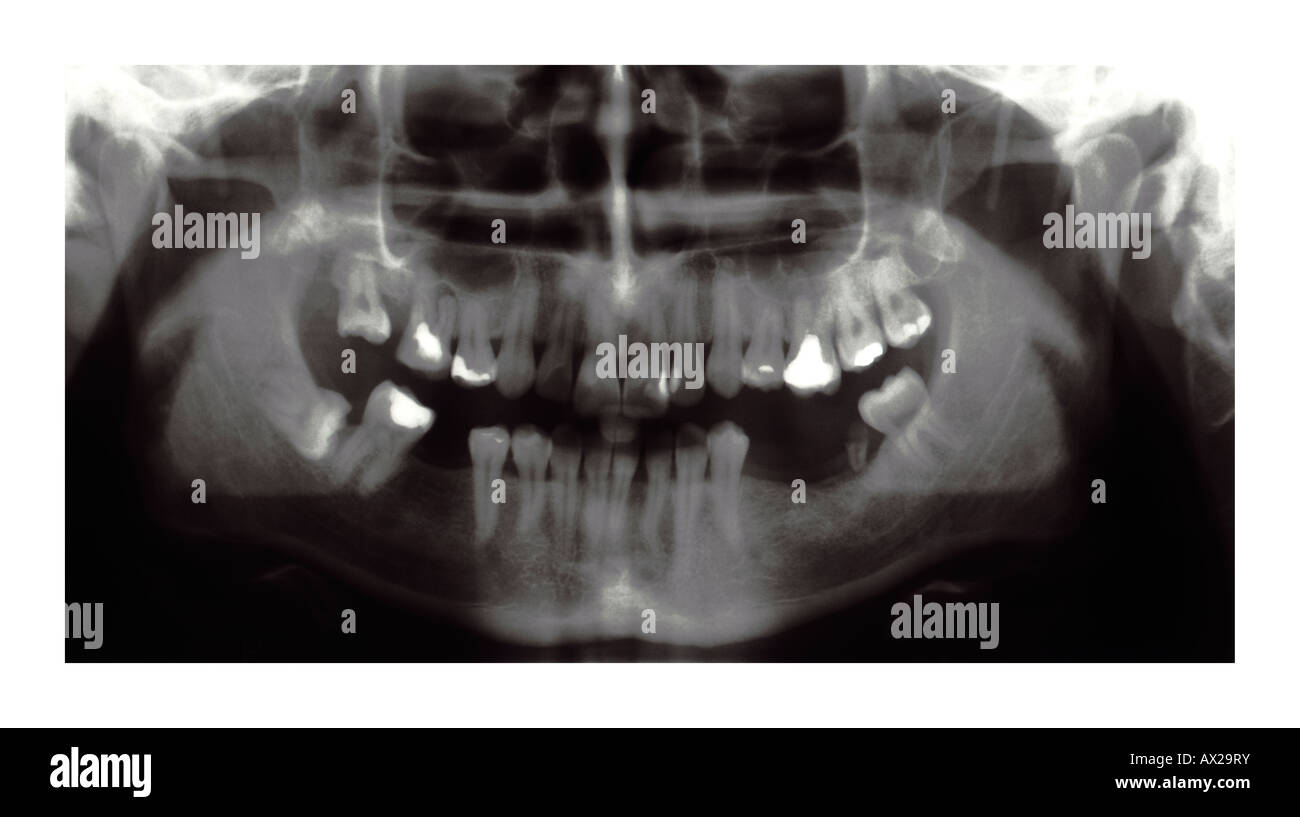

Panorex dental. This image is exceptionally useful in diagnosing a wide range of issues. The image is either displayed digitally on a computer or. Without this critical piece of data we can sometimes miss pathologic lesion such as tumors or cysts extra teeth and a whole host of other conditions that need surgical treatment in a timely fashion.

Now a standard part of the imaging protocols at many practices digital panoramic x-rays provide a large amount of diagnostic information and great efficiency. OPG otherwise known as panorex or orthopantomogram is a full mouth panoramic scan dental x-ray of the lower and upper jaws. Our Technology June 20 2018 by Reedley Dental 0.

Diagnostic images of a patients complete dentition are produced almost instantly with a digital panoramic imaging system and the newest systems provide. It is commonly performed by dentists and oral surgeons in everyday practice and. Tracy Robinson is a well-trained Veneta Dentist call us today. Dental Digital Panoramic X-ray. Without this critical piece of data we can sometimes miss pathologic lesion such as tumors or cysts extra teeth and a whole host of other conditions that need surgical treatment in a timely fashion. Initially the patient will sit in a chair with their chin on a small ledge. Now a standard part of the imaging protocols at many practices digital panoramic x-rays provide a large amount of diagnostic information and great efficiency. Your dental hygienist doesnt have to constantly come in and out of the room to change film saving you time. During the panorex X-ray the patient is asked to bite down on a special tool that assists the operator in positioning the patients head in the correct position.

A panorex is imaging machinery that is capable of providing a full view of the upper and lower jaws teeth temporomandibular joints and sinuses. Dimensions of Dental Hygiene is a monthly peer-reviewed journal that reconnects practicing dental hygienists with the nations leading educators and researchers. Access Dental providing professional dental care. It is commonly performed by dentists and oral surgeons in everyday practice and. Here you can discover how panoramic radiography works. This image is exceptionally useful in diagnosing a wide range of issues. Welcome to the new age of dental x-ray technology.